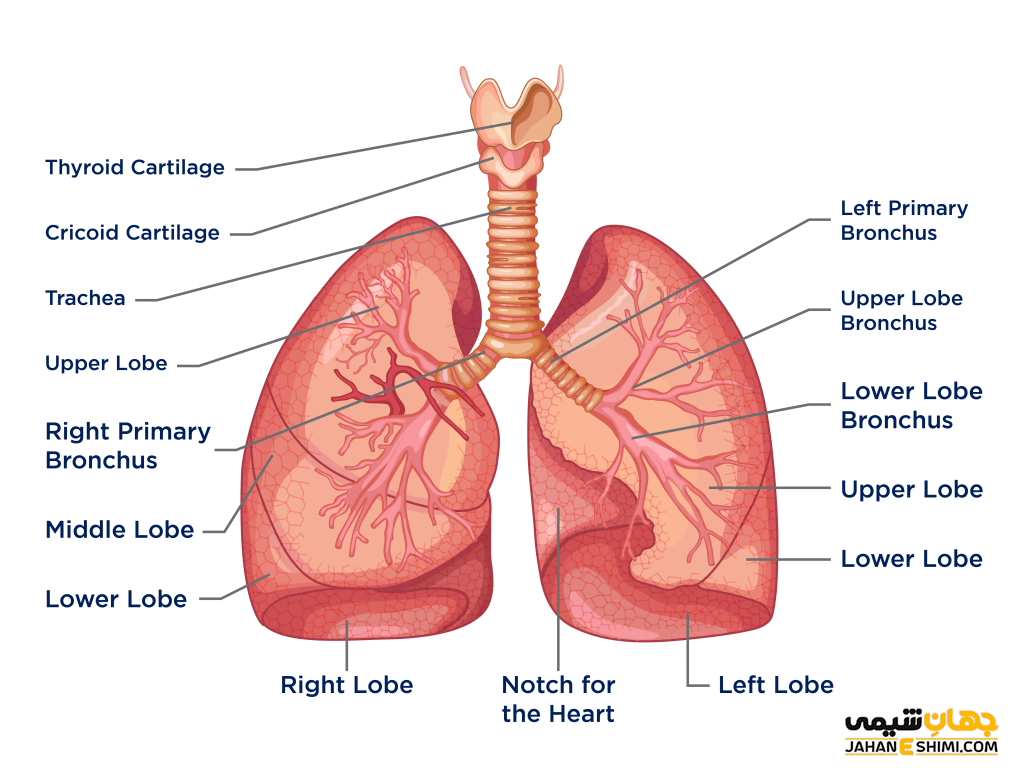

ریه ها در هر دو طرف مدیاستنوم ، درون حفره قفسه سینه قرار دارند. هر ریه توسط یک حفره پلور احاطه شده است که توسط پلور احشایی و جداری ایجاد می شود.

ریه ها ساختاری تقریباً به شکل مخروط با یک راس ، پایه ، سه سطح و سه حاشیه هستند. ریه چپ کمی کوچکتر از راست است – این به دلیل وجود قلب است. هر ریه شامل:

راس – انتهای فوقانی ریه به سمت بالا ، بالاتر از سطح دنده ۱ و در کف گردن قرار می گیرد.

پایه – سطح تحتانی ریه که بر روی دیافراگم قرار دارد.

لوب ها (دو یا سه) – این ها با شکاف در ریه از هم جدا می شوند.

لوب های ریه

ریه های راست و چپ ساختار لوبولار یکسانی ندارند. ریه راست دارای سه لوب است. فوقانی ، میانی و تحتانی. لوب ها توسط دو شکاف از یکدیگر جدا می شوند:

شکاف مورب – از حاشیه تحتانی ریه در جهت فوق خلفی حرکت می کند ، تا زمانی که مرز خلفی ریه را پیدا کند.

شکاف افقی – به صورت افقی از جناغ ، در سطح دنده ۴ ، برای رسیدن به شکاف مورب اجرا می شود. ریه چپ حاوی لوب های فوقانی و تحتانی است که با یک شکاف مورب از هم جدا می شوند.

ریشه ریه مجموعه ای از ساختارها است که ریه را از مدیاستن معلق می کند. هر ریشه شامل یک برونش ، شریان ریوی ، دو رگ ریوی ، رگ های برونش ، شبکه اعصاب ریوی و عروق لنفاوی است. تمام این ساختارها از طریق هیلوم وارد ریه می شوند یا از ریه خارج می شوند – ناحیه ای به شکل گوه در سطح مدیاستال قرار دارد.

درخت برونشیال مجموعه ای از راه ها است که هوا را به آلوئول های ریه می رساند. این قسمت از نای شروع می شود و به برونش چپ و راست تقسیم می شود.

هر برونش با عبور از هیلوم وارد ریشه ریه می شود. در داخل ریه ، آنها تقسیم می شوند و برونش های لوبار را تشکیل می دهند که هر کدام هوای یک لوب را تأمین می کند.